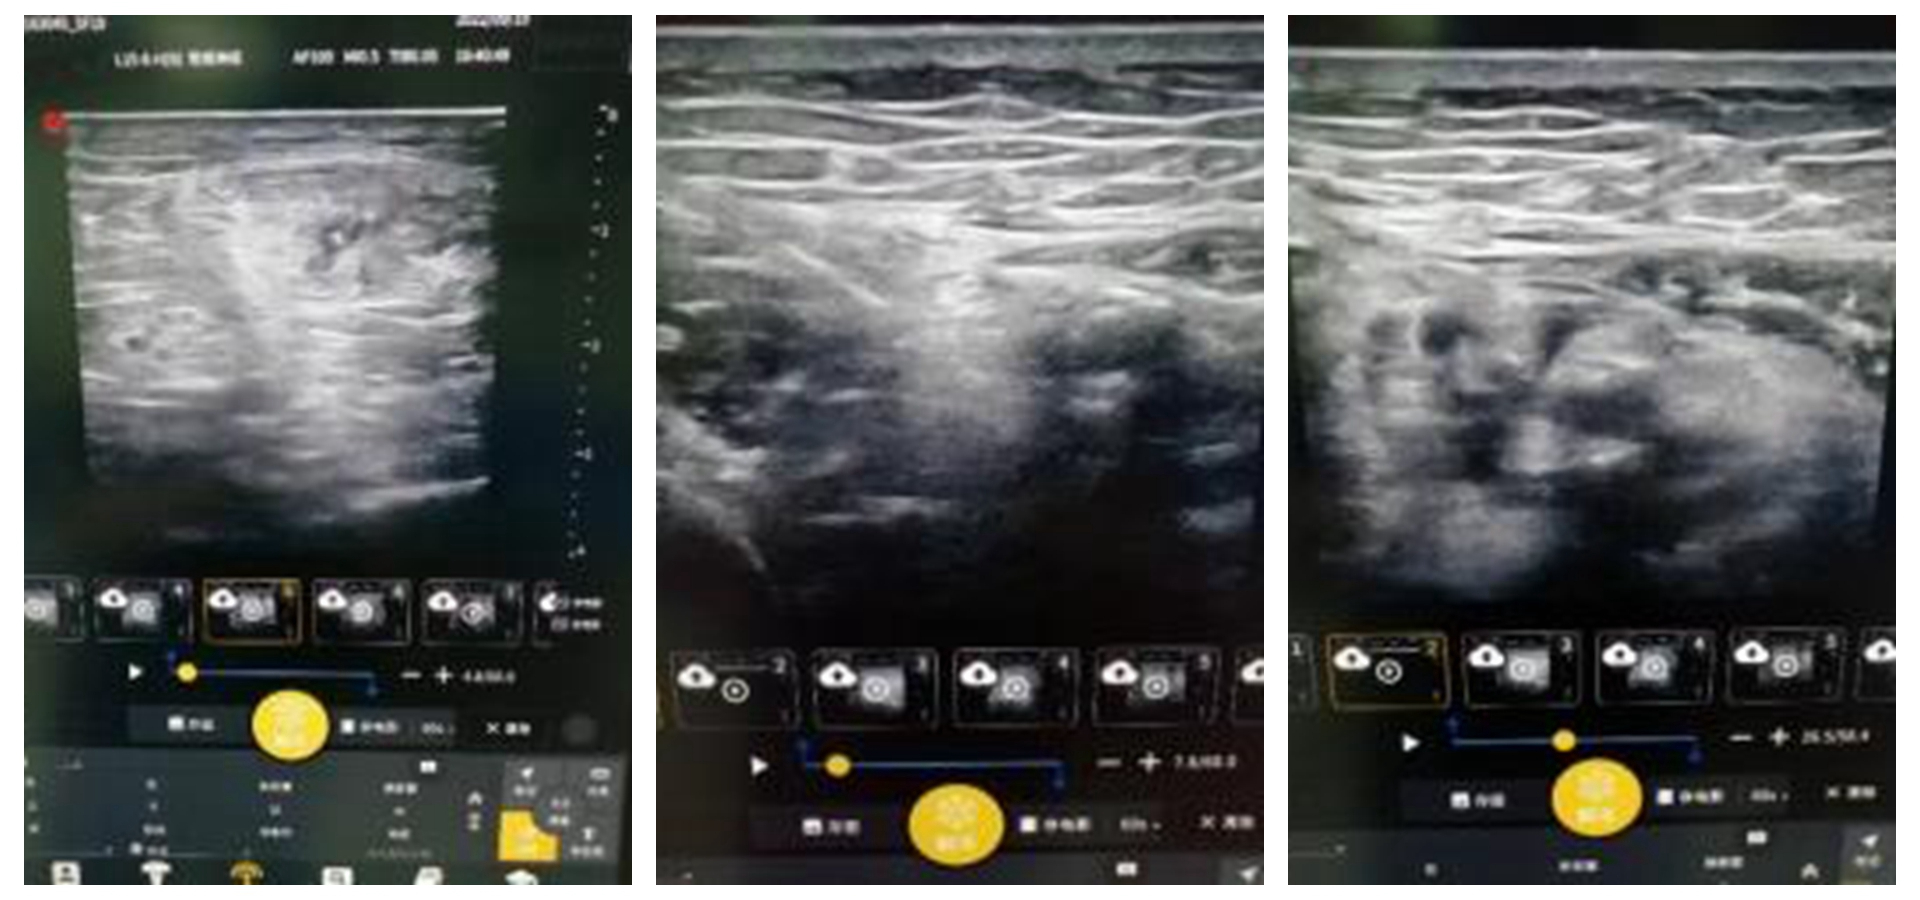

近日,我院麻醉科成功实施超声引导下神经阻滞麻醉为一名患者行急症手术。 该患者病情危重复杂,麻醉科主任康荣田组织麻醉科全科进行病例讨论,经过参会各位专家的分析和研讨,大家认为:患者病情危重,合并症多,各重...